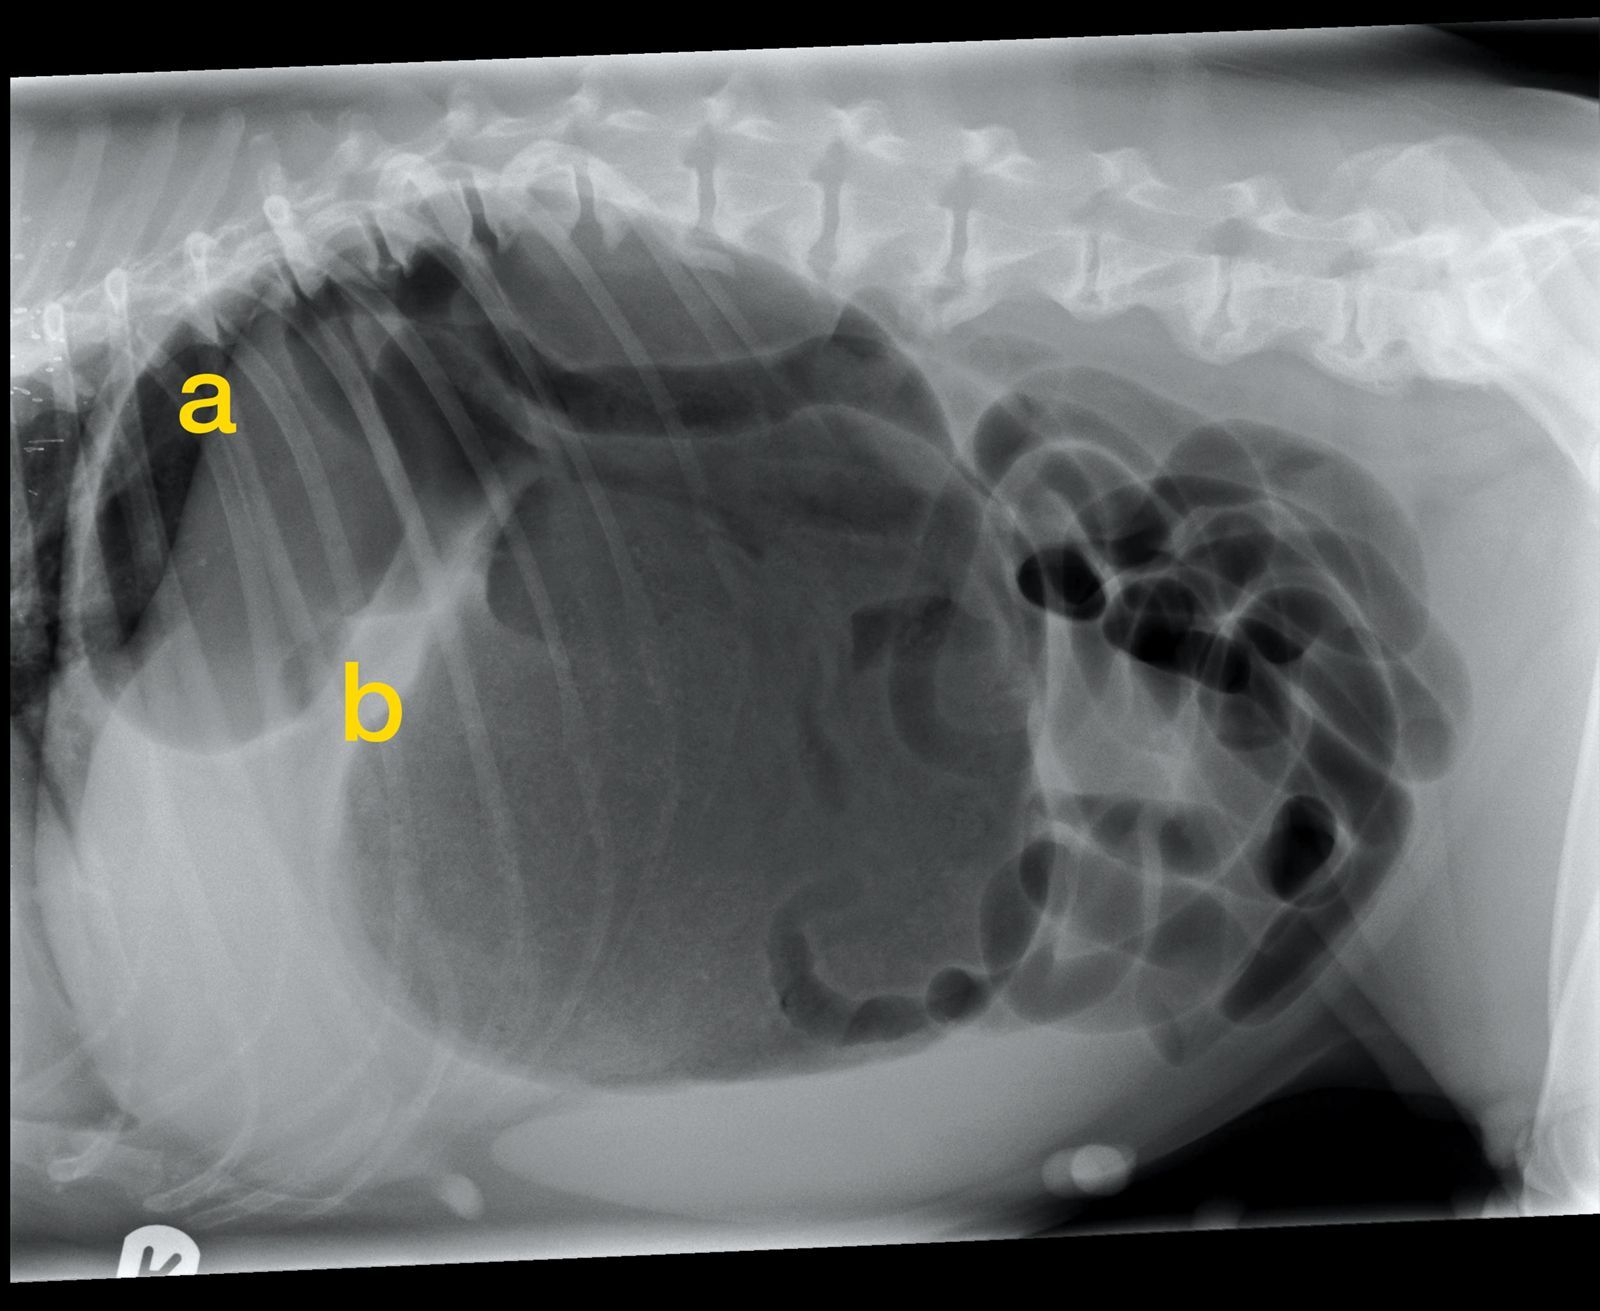

WebLa torsión gástrica es una afección grave y potencialmente mortal, que afecta especialmente a las razas de perros de mayor tamaño. Pese a ello, no hay que. WebSe cree que si hay suficiente espacio en el abdomen para que los órganos llenos de gas se muevan, entonces ocasionalmente lo harán. Por este motivo, la. WebLa torsión de estómago o intestino delgado es una causa frecuente de muerte súbita en los cerdos en crecimiento y a menudo afecta a los mejores cerdos del grupo. También se. WebEl signo típico en una TC del infarto omental es la presencia de un patrón de rayas concéntricas hiperatenuadas en la masa grasa, llamado «signo del giro» 9. Sin. WebUna torsión testicular es una urgencia médica. Ocurre cuando el cordón espermático, que suministra sangre a los testículos, rota y se retuerce. Esta torsión interrumpe el. WebLa torsión (vólvulo) se produce cuando todo el estómago se retuerce en el interior del abdomen de forma que queda cerrado tanto en su entrada como en su salida, como una. Web6.2.1 Torsión-dilatación gástrica (GDV) Es la rotación de un estómago distendido hacia su eje mesentérico. Es una patología que amenaza la vida y que da lugar a obstrucción. WebTorsión de estómago: causas, síntomas, prevención y tratamiento. La torsión gástrica o torsión de estómago es una de las enfermedades más graves que. WebCualquier perro puede desarrollar una GDV, pero es más común en algunas razas que en otras. Las razas de perros grandes con pechos profundos y estrechos,. WebUna torsión de estómago es una patología que progresa rápidamente y puede derivar en la muerte del paciente, si no se realiza una intervención de urgencia. Hay perros que.